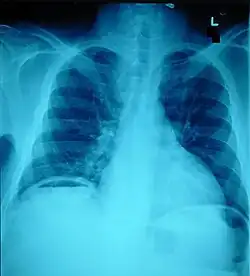

Pneumoperitoneum, seen as an air bubble on the lower left side of the X-ray film

The small intestine takes up a large part of the abdomen and is likely to be damaged in penetrating injury.[5] The bowel may be perforated.[4] Gas within the abdominal cavity seen on CT is understood to be a diagnostic sign of bowel perforation; however intra-abdominal air can also be caused by pneumothorax (air in the pleural cavity outside the lungs that has escaped from the respiratory system) or pneumomediastinum (air in the mediastinum, the center of the chest cavity).[4] The injury may not be detected on CT.[4] Bowel injury may be associated with complications such as infection, abscess, bowel obstruction, and the formation of a fistula.[4] Bowel perforation requires surgery.[4]